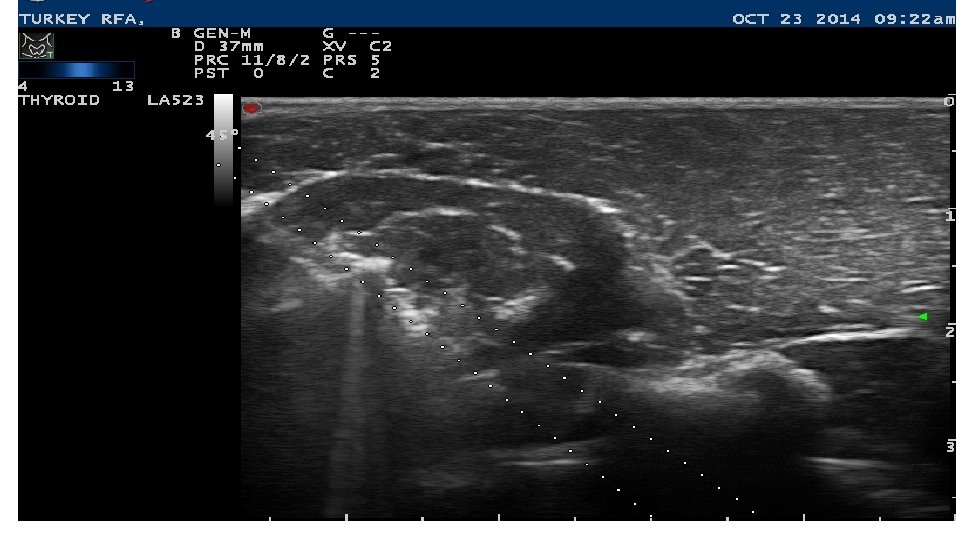

Background in RFA prior to 2017 • 1. Spent time in Reggio Emilia with Roberto Valcavi training in RFA with Korean Thyroid RF Mini Probe from Star Med. • 2. Spent 2 months using the Medtronic larger probe in my office doing work on technique for RFA for thyroid nodules learned in Italy. • 3. Medtronic decided not to fund any further work on thyroid and stopped their smaller probe from completing FDA approval. • 4. Star Med was presented with our plan 3 years ago for initial study but has not obtained FDA approval to this day. • 5. Our thyroidology interventional group Dan Duick, Mark Lupo and myself kept hopes alive and we hope the time has come to get RFA off the ground in the USA.